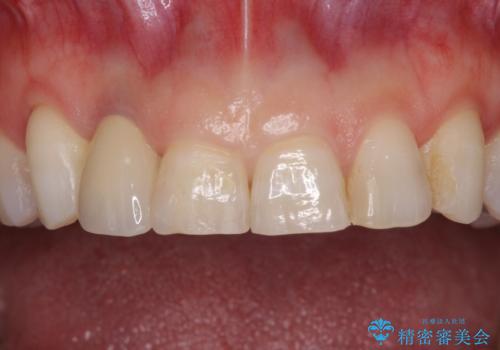

歯肉が腫れている前歯 外科処置を併用したオールセラミッククラウン

- 前歯のクラウン周りに歯肉が腫れていることを気にして来院された患者様です。

元々磨き残しによる歯肉の腫脹がありましたが、クラウンが歯肉深くに装着されていたため、特に腫脹が目立っていました。

仮歯に置き換えた際に歯周外科処置を行い、歯肉の腫脹が落ち着いたことを確認してオールセラミッククラウンにて補綴することとしました。

外科処置後の痛みを気にしていましたが、小規模の処置であったため、痛みを感じることはほとんどありませんでした。

気になっていた腫脹がなくなり、患者様には大変満足していただきました。